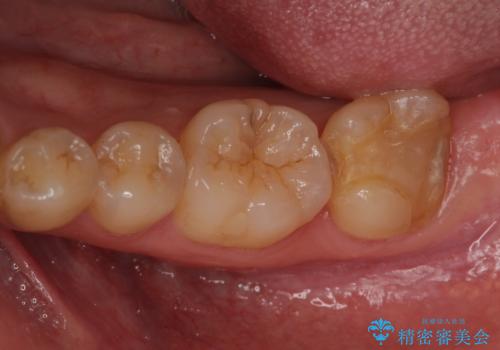

[歯と歯の間の虫歯] ジルコニアクラウン

- メンテナンスの患者様です。レントゲンで歯と歯の間の虫歯が発見されたため治療を行うことになりました。

歯質全体が粗造になっており、インレー治療だと虫歯になる可能性があるので被せ物での治療となりました。

適合が良い被せ物が入りました。

毎日フロスや歯間ブラシを行うことで歯と歯の間が虫歯になるリスクが低くなります。